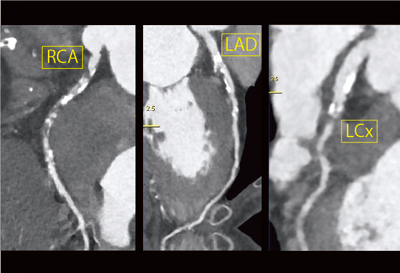

冠動脈の石灰化が非常に強く,冠動脈CTでの評価は容易ではない(図4)。curved MPR画像にて,LCX #13に強い狭窄があることは確認できたものの,RCAステント留置部やLAD,対角枝については,はっきりと評価できない(図5)。

![]() 図5 症例2:curved MPR画像 |